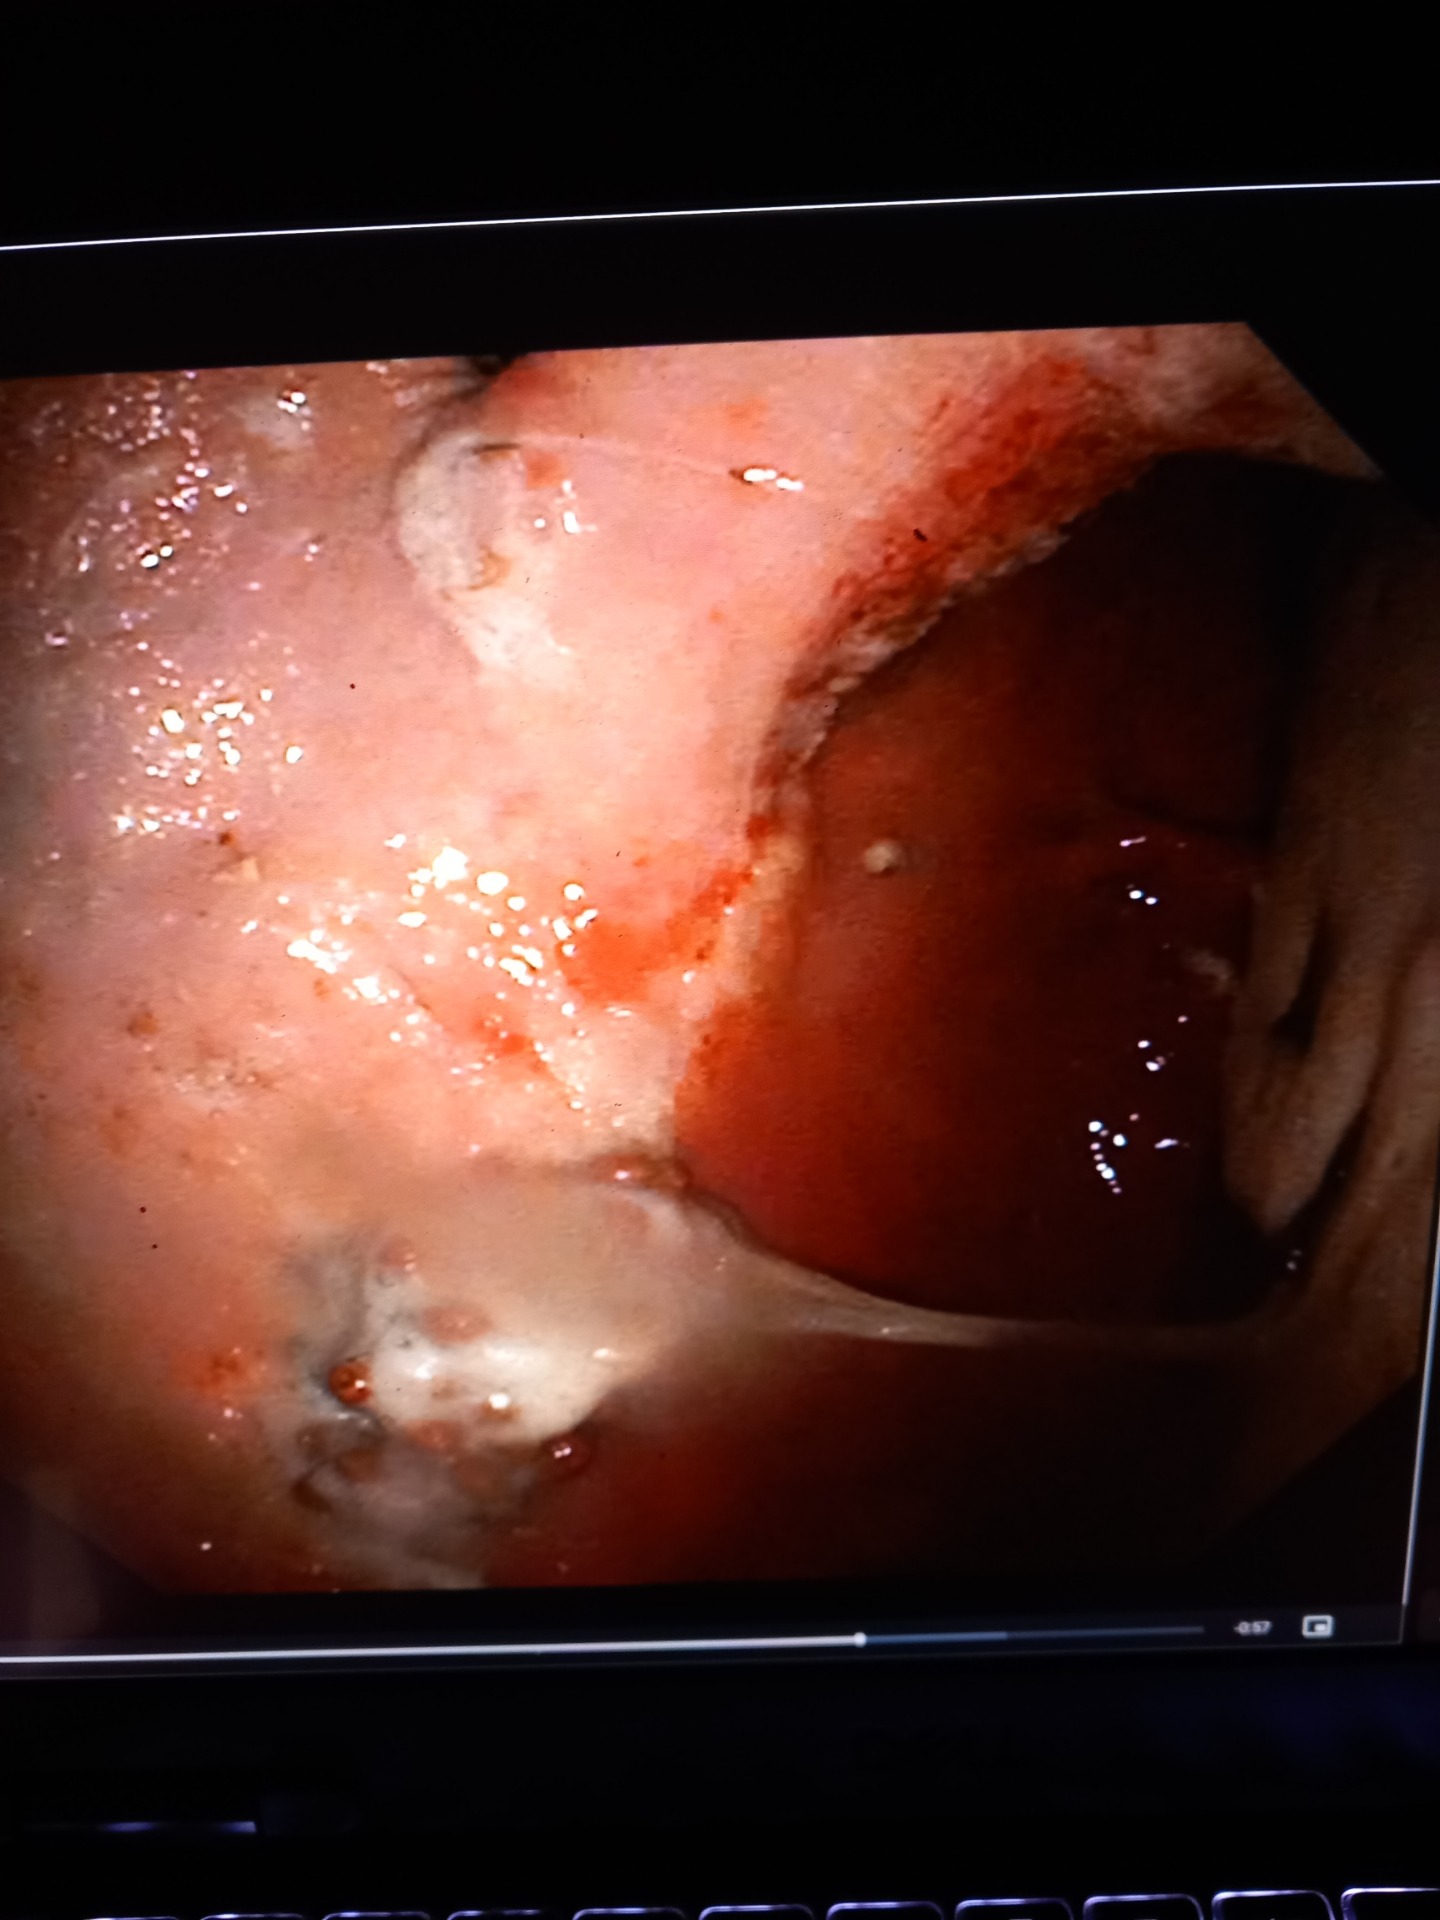

Gastroscopie - Endoscopie

Sinds kort heb ik de mogelijkheid om ook gastroscopieën aan te bieden. Met een camera kijken we in de maag van je paard, op zoek naar maagzweren, impacties of andere problemen. Na dit onderzoek krijg je een uitgebreid behandelplan mee.

Met de camera kunnen we ook de neusgangen, keel, luchtzakken en luchtpijp bekijken. Dit is zeer interessant bij paarden met klachten van neusbloeden, hoesten, astma, verminderde prestatie.

Aangezien we het probleem kunnen visualiseren kunnen we een betere diagnose stellen en een aangepaste behandeling opstarten. Nog een voordeel is dat we stalen kunnen nemen via de scoop.